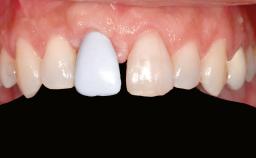

Ridge Preservation and Implant Placement for a Fixed Dental Prosthesis After a Car Accident

It is well known to clinicians that any removal of teeth will, over time, cause the dimensions of the alveolar ridge to be reduced by resorption of the bundle bone and by changes related to external modeling. This development is particularly evident in the crestal region with its thin buccal bone that consists of bundle bone almost entirely. The facial bone will rapidly resorb as blood supply from the periodontal ligament gets disrupted (Araújo and Lindhe 2005). There is no reason why traumatic tooth loss should not have the same consequences. It takes more than achieving implant osseointegration for a treatment outcome to be considered successful. No deficiency of bone or soft tissue is acceptable when an ideal esthetic outcome is the goal. Several articles (Sanz and coworkers 2011; Vignoletti and coworkers 2011) have reported on techniques of improving the alveolar ridge for implant treatment, notably focusing on protecting tissues from resorption.

Prosthesis Type FDP